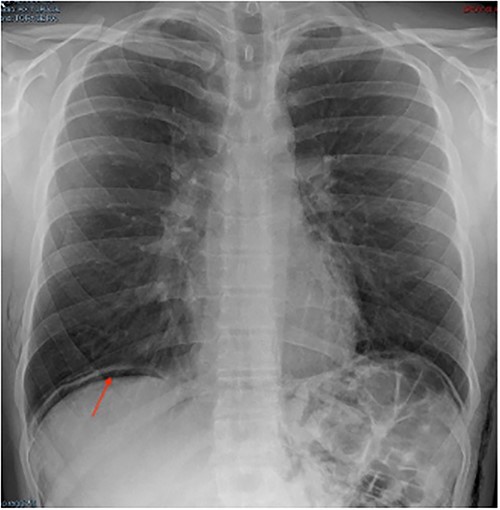

In the post-operative day (POD) I, the patient was referred to our emergency department due to thoracic pain. The patient’s general conditions were good except for a subcutaneous emphysema extended to thorax, abdomen, back and scrotum. A chest X-ray showed a suspected image of free intraperitoneal gas (Fig. 1); we, therefore, decided to perform further radiological study.